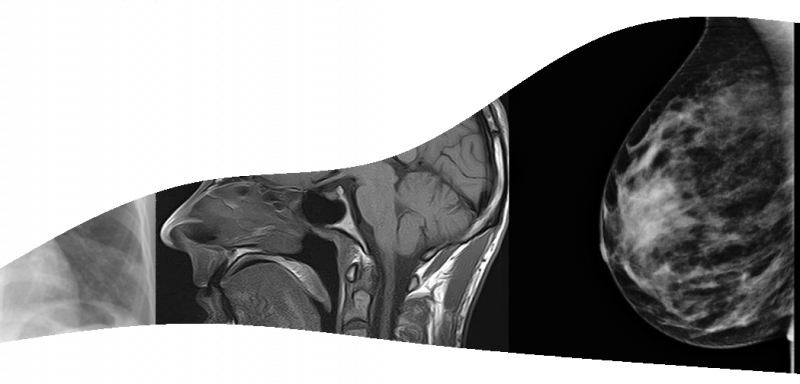

• Centre d’Imagerie Médicale

Radiologie du Baillius

Le centre de Radiologie du Baillius réalise ses examens sur baillargues , mais aussi à la clinique du Millénaire pour ce qui concerne les examens d'IRM.